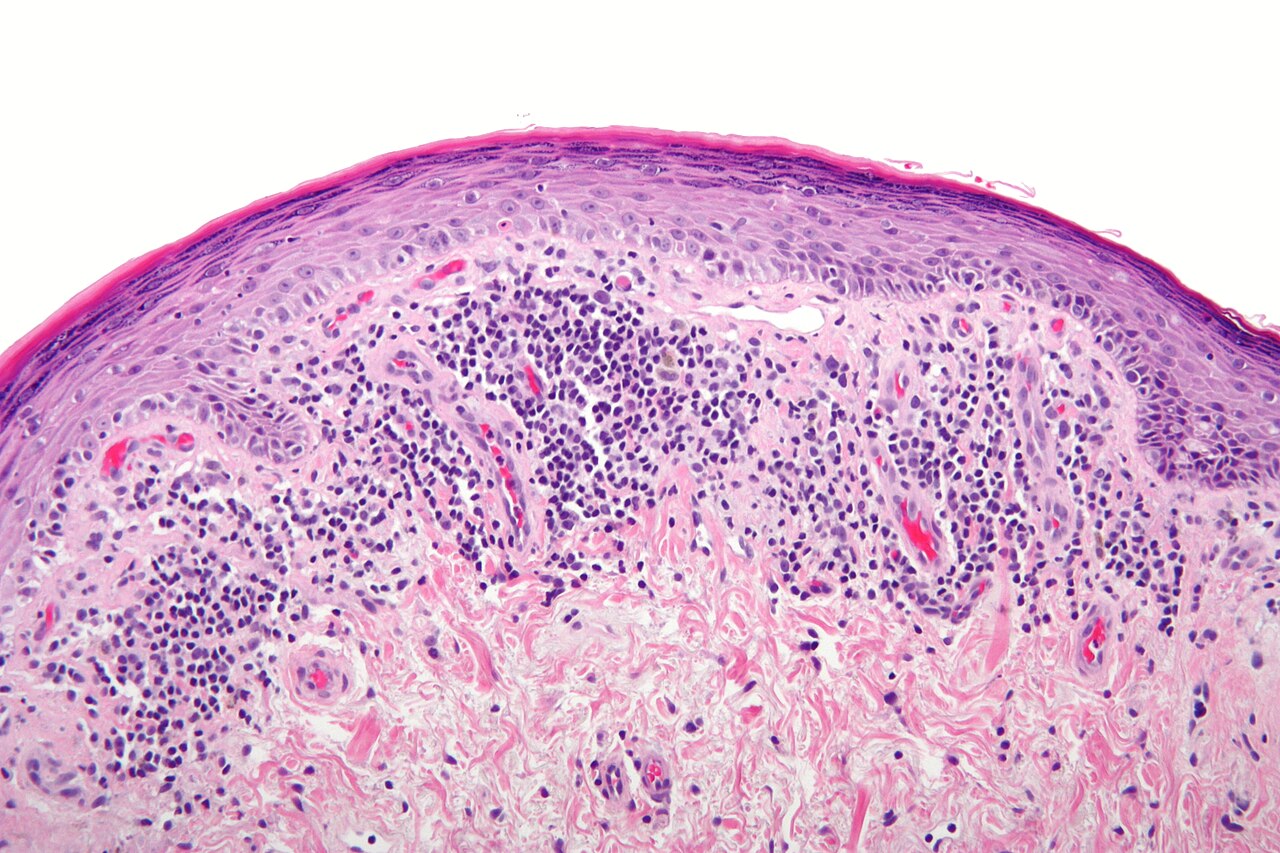

Nephron, CC BY-SA 3.0, via Wikimedia Commons

A skin condition that involves a rash with itchy, purplish lesions that develop in one area of your body or in several regions, lichen planus is a lichenoid dermatosis. It is largely believed to be an autoimmune disorder with symptoms of inflammation where immune T-cells attack the protein in the skin and mucus membranes. The disorder is also associated with fatigue, depression, anxiety, and overall lower quality of life. It is most common in people between the ages of 30 and 60. There are several types of lichen planus, which we will explore below.

Impacting the skin, this type is known for its flat, purplish lesions that arise over several weeks. They can also be scaly patches that itch. It typically affects the face, nape of the neck, arms, back of the hands, skin folds (armpits and groin), scalp (lichen planopilaris) with corresponding hair loss, and the nails — causing splitting, ridging, thinning, and discoloration. Cutaneous lichen planus tends to resolve over time on its own without treatment.